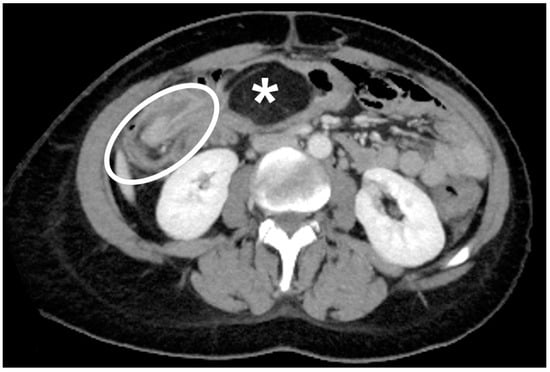

The authors observed a case of colonic lipoma causing intussusception. The data of the patients were pooled in the review. The patient had been reporting diffuse and intermittent abdominal pain for one year. An ultrasound scan was performed, and it showed only biliary sludge. The patient began medical therapy for which she showed improvement. A worsening of the clinical condition in the following two months, associated with the onset of diarrhea, led the patient to be reevaluated for her condition. In this case, a CT scan was performed (Figure 2 and Figure 3).

Figure 2.

Axial CT scan of the abdomen in portal/venous phase. A rounded, smoothly outlined and sharply demarcated abdominal mass, having fat attenuation mass with fat attenuation (asterisk) is observed. A circumferential thickening in ileocolic intussusception caused by the lipoma can be seen (white circle).